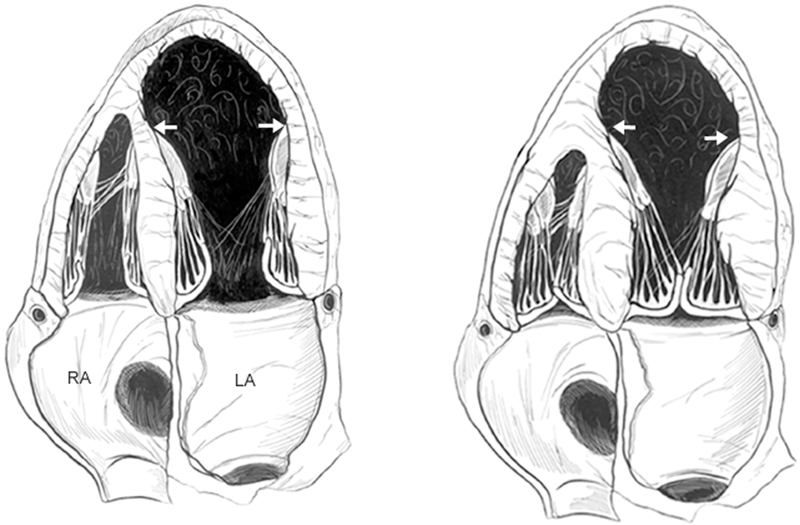

فحوصات تشخيصية لبعض امراض القلب والشرايين التاجية